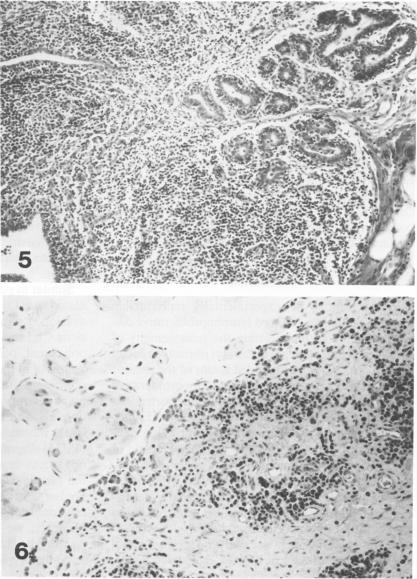

For investigation of the pathogenicity of lentivirus strains, which have distinctly different cytopathic phenotypes in synovial membrane cell culture, plaque-purified, lytic, and nonlytic ovine lentivirus (OvLV) isolates were inoculated intratracheally into two groups of neonatal lambs. Twelve lambs were inoculated with a lytic OvLV isolate and 3 lambs each with two nonlytic OvLV isolates. Five control lambs were inoculated with either virus-free medium or were left uninoculated. In 8 of 12 lambs inoculated with a lytic OvLV isolate mild to severe lesions of lymphoid interstitial pneumonia (LIP) and pulmonary lymphoid hyperplasia developed, 6 of 12 lambs had lesions of pulmonary lymph node follicular hyperplasia, 3 of 9 female lambs had lesions of lymphoproliferative mastitis, 3 of 10 lambs had lesions of lymphocytic/plasmacytic synovitis, and 3 lambs had no lesions. In 3 of 6 lambs inoculated with nonlytic OvLV isolates only mild LIP lesions developed, without concurrent mammary gland or joint lesions. Bronchoalveolar lavage samples from OvLV-diseased lambs contained on average 1.5-fold more numbers of total leukocytes, and 4-fold more numbers of lymphocytes, compared with bronchoalveolar lavage samples of normal lambs. Monoclonal antibodies to ovine lymphocyte surface markers showed that the SBU-T8+ lymphocyte (CD 8 equivalent) was the predominant lymphocyte subset (mean of 65% of total lavaged lymphocytes) in bronchoalveolar lavage samples of 3 diseased lambs. Ovine lentivirus was reisolated from multiple tissues of both groups of OvLV-inoculated lambs, but the percentage of individual tissues infected was greater in lambs inoculated with the lytic viral isolate. Control lambs had no lesions and failed to produce OvLV-specific antibodies or yield OvLV from tissues. All OvLV-inoculated lambs produced either low or undetectable serum virus neutralizing antibodies. In contrast, lambs inoculated with either lytic or nonlytic OvLV produced precipitating antibodies to OvLV glycoprotein and group-specific protein. However, initial detection of precipitating antibodies to OvLV glycoprotein was earlier (mean, 5.8 weeks after inoculation) in OvLV-infected lambs in which severe lymphoproliferative disease developed and delayed (mean, 10.2 weeks after inoculation) in OvLV-infected lambs with mild or no lesions. Together, these results suggest that lentivirus isolates produced disease in a virus strain-dependent manner and suggest that humoral immune responses against OvLV failed to prevent lesion development in lentivirus-infected lambs.(ABSTRACT TRUNCATED AT 400 WORDS)

为研究在滑膜细胞培养中具有明显不同细胞病变表型的慢病毒株的致病性,将空斑纯化的、溶细胞性和非溶细胞性绵羊慢病毒(OvLV)分离株经气管内接种到两组新生羔羊体内。给12只羔羊接种溶细胞性OvLV分离株,给3只羔羊分别接种两种非溶细胞性OvLV分离株。5只对照羔羊接种无病毒培养基或不接种。在接种溶细胞性OvLV分离株的12只羔羊中,8只出现了轻度至重度的淋巴间质性肺炎(LIP)和肺淋巴组织增生病变,12只中有6只出现肺淋巴结滤泡增生病变,9只雌性羔羊中有3只出现淋巴增生性乳腺炎病变,10只羔羊中有3只出现淋巴细胞/浆细胞性滑膜炎病变,3只羔羊无病变。在接种非溶细胞性OvLV分离株的6只羔羊中,3只仅出现轻度LIP病变,无乳腺或关节并发病变。与正常羔羊的支气管肺泡灌洗样本相比,OvLV患病羔羊的支气管肺泡灌洗样本中总白细胞数量平均多1.5倍,淋巴细胞数量多4倍。针对绵羊淋巴细胞表面标志物的单克隆抗体显示,在3只患病羔羊的支气管肺泡灌洗样本中,SBU-T8 +淋巴细胞(相当于CD 8)是主要的淋巴细胞亚群(平均占总灌洗淋巴细胞的65%)。从两组接种OvLV的羔羊的多个组织中重新分离出绵羊慢病毒,但接种溶细胞性病毒分离株的羔羊中单个组织的感染百分比更高。对照羔羊无病变,未产生OvLV特异性抗体,也未从组织中分离出OvLV。所有接种OvLV的羔羊产生的血清病毒中和抗体水平低或检测不到。相比之下,接种溶细胞性或非溶细胞性OvLV的羔羊产生了针对OvLV糖蛋白和群特异性蛋白的沉淀抗体。然而,在发生严重淋巴增生性疾病的OvLV感染羔羊中,针对OvLV糖蛋白的沉淀抗体的初始检测较早(接种后平均5.8周),而在病变轻微或无病变的OvLV感染羔羊中则延迟(接种后平均10.2周)。总之,这些结果表明慢病毒分离株以病毒株依赖的方式引发疾病,并表明针对OvLV的体液免疫反应未能预防慢病毒感染羔羊的病变发展。(摘要截于400字)